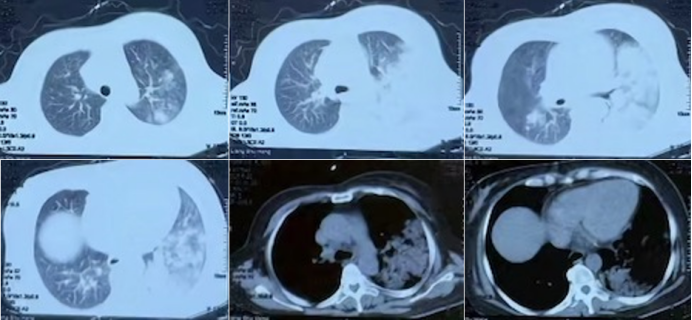

• CT(2025-05-29,外院):双肺多叶段渗出样病变,以左肺舌叶和左下叶为主,少量胸腔积液(图1)

1  患者肺CT(2025-05-29)

在此基础上,医疗团队携带氧气袋为患者复查胸部CT结果显示,患者肺内渗出性阴影较前明显吸收(图3),进一步印证了治疗方案的有效性。

3  治疗前后肺CT比较